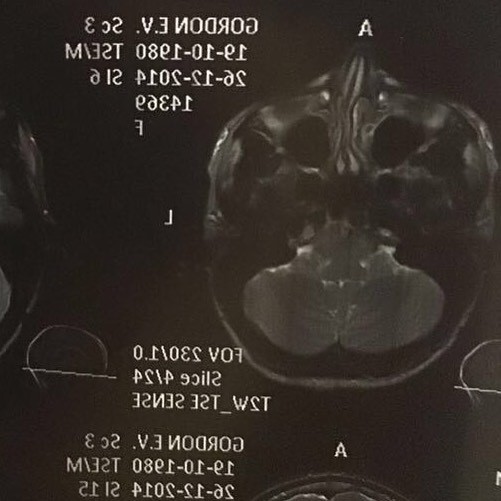

35-летняя певица Катя Гордон долгое время чувствовала себя неуверенно из-за своего носа. А несколько недель назад решила избавиться от своего недостатка. На своей странице в Instagram девушка показала, каким её нос был до операции.

Она была смещена и сломана, как у участников боёв без правил. У меня были травмы, и я давно мечтала "починить" свой нос. Последние съёмки моего клипа "Танцуй" стали решающими — мы фактически не смогли вставить ни одного кадра, где я пою в фас, только с правой щеки. Врача я выбирала больше года: мне не хотелось, чтобы мне сделали курносый нос, хотелось сохранить свою индивидуальностьКатя Гордон.

Как известно из её биографии, нос деформировался после того, как в 2011 году её избил собственный муж − адвокат Сергей Жорин. Тогда Катерина попала в больницу с сотрясением мозга и многочисленными ушибами. К слову, в 2014 году Катя вернулась к Сергею Жорину.